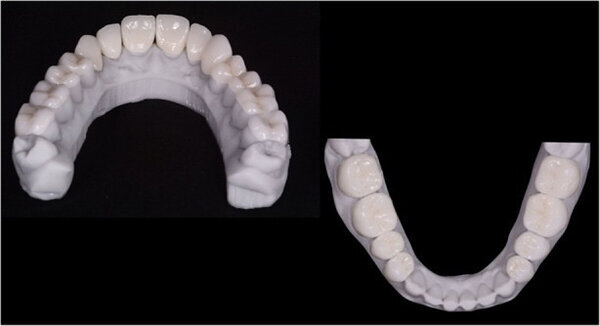

Fig. 12. Carillas y coronas finales preparadas digitalmente con el software de diseño Ceramill Mind y producidas en una fresadora (Ceramill Motion 2) a partir de bloques de cerámica de disilicato de litio mecanizables (VITABLOCS TriLuxe forte).

Las carillas y coronas finales se prepararon digitalmente usando el software de diseño Ceramill Mind (Amann Girrbach) y se produjeron en una fresadora (Ceramill Motion 2, Amann Girrbach) a partir de bloques de cerámica de disilicato de litio mecanizable (VITABLOCS TriLuxe forte para Ceramill Movimiento 2, Amann Girrbach; Fig.10). Después de confirmar el sellado marginal y las propiedades visuales mediante la inserción de prueba, se colocó un retractor de labio y mejilla (OptraGate, Ivoclar Vivadent) en la boca del paciente.